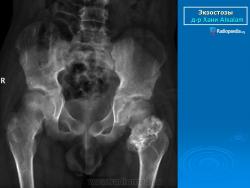

Локализация остеохондромы: частота поражения отдельных костей различна; нижний коней бедренной кости, верхние отделы плечевой и большеберцовой костей поражаются более чем у половины больных. На всем протяжении остеохондрома покрыта надкостницей. Она может быть обнаружена и в других костях, за исключением костей лицевого черепа. Все же поражение костей позвоночника, кистей рук и стоп встречается редко. При рентгенологическом исследовании видна типичная картина узкого или широкого выроста вблизи эпифизарной части пораженной кости. Обычно плотность узла неоднородная, имеются многочисленные плотные участки, соответствующие обызвествленным хрящевым долькам. Хрящевая «шапочка» большей частью не определяется, поскольку хрящ остается необызвествленным. Она может быть выявлена только при магнитно-резонансной томографии.